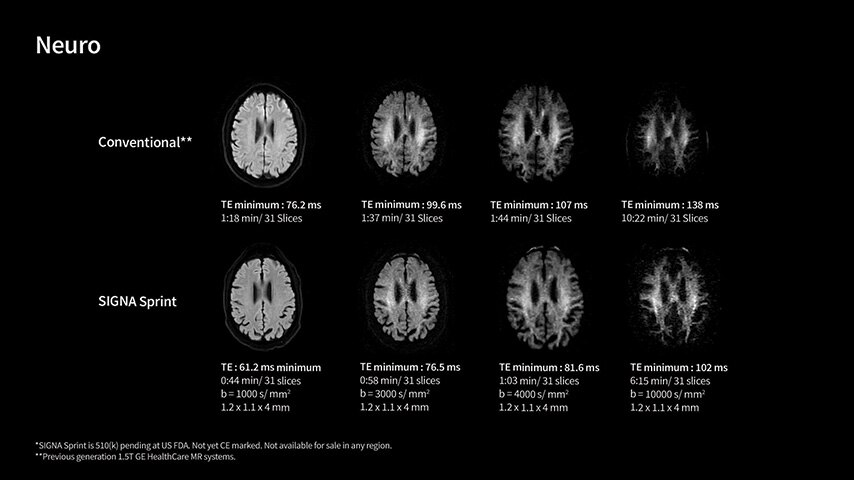

In oncological assessments, diffusion imaging is a critical clinical indicator. SIGNA Sprint offers clearer diffusion, reduced distortion, and improved SNR.¹

Within cardiovascular diseases, the functional assessment of the heart is an essential imaging application. SIGNA Sprint is powered by built-in AI technologies—Sonic DL™, AIR Recon DL and AIR x™—enabling high-quality imaging even in the most demanding anatomies.

Imaging capabilities to unlock the power to explore further

High gradient performance

The growing clinical need within oncology and cardiology requires an MRI scanner that can rise to the challenge. With a high gradient performance of 65/200, SIGNA Sprint helps deliver crystal-clear imaging for ultimate diagnostic confidence. Improved signal-to-noise ratio (SNR) and diffusion, with deep-learning solutions that could enhance diagnostics and treatment response monitoring in your oncology patients.¹ Additionally, the shift from qualitative to quantitative cardiac MRI reduces the time and expertise needed to interpret scans and offers greater consistency and reliability. Helping you to unlock the power to explore further - even in your most challenging cases.